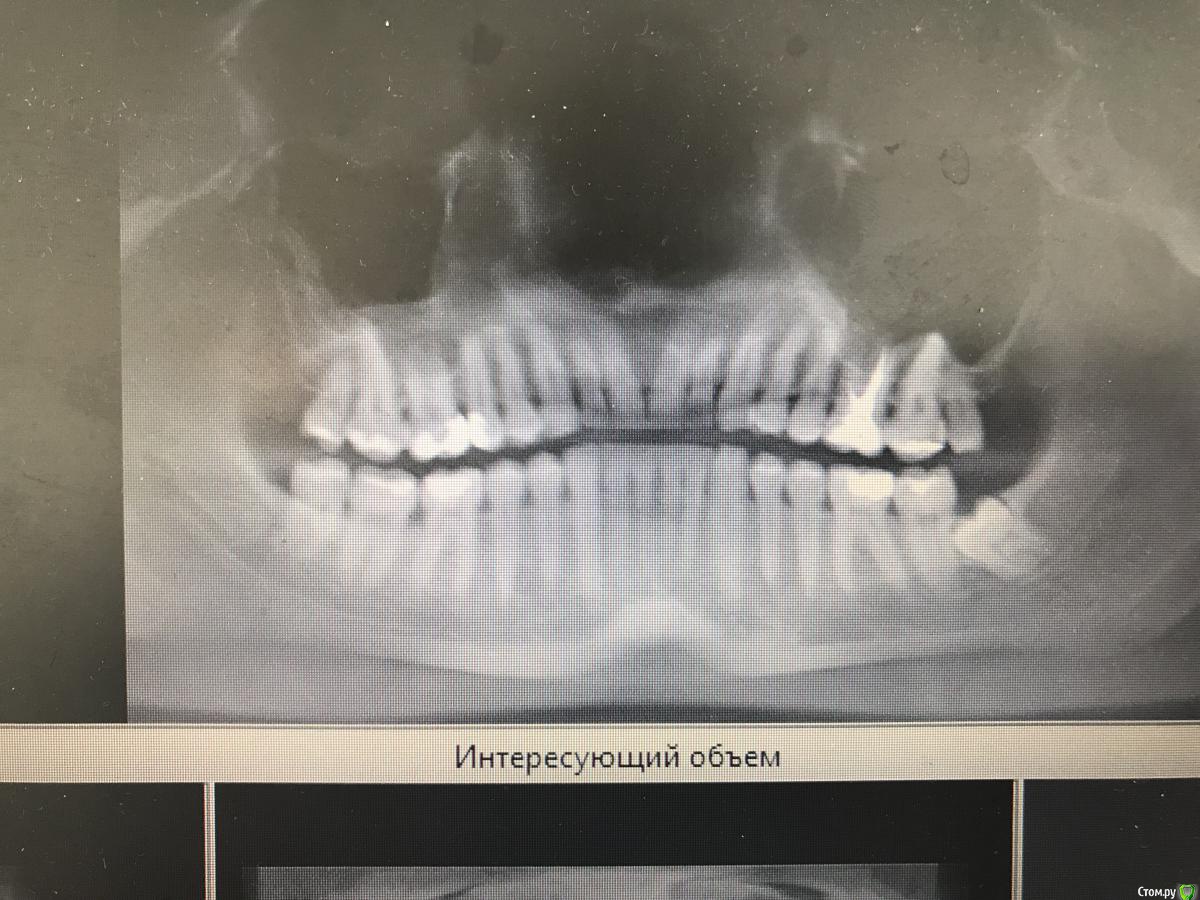

dr.Dre Опубликовано 6 июня, 2018 Поделиться Опубликовано 6 июня, 2018 (изменено) Добрый день ,коллеги такой клинический случай ,пациента нос заложен постоянно лор напривил сказал гайморит от зубов ,я думаю , что причина в 26 ,что скажите? Изменено 6 июня, 2018 пользователем dr.Dre Ссылка на комментарий

Дмитрий Л. Опубликовано 6 июня, 2018 Поделиться Опубликовано 6 июня, 2018 извините пожалуйста загрузил с телефона, у меня есть кт как можно загрузить на форум?Загрузить на файлообменник или облако (гугл диск, к примеру) и затем ссылку сюда. Я бы обратил внимание на 16. Но данных мало вы предоставили... гайморит... какой, 1-, 2-сторонний? Срезы непонятные Заложенность носа это ещё не гайморит. Жалобы на "зубы"? Перкуссия и т.д. Ссылка на комментарий

johniola Опубликовано 7 июня, 2018 Поделиться Опубликовано 7 июня, 2018 Где там гайморит? Геморрой может и есть,а вот гайморита не вижу Ссылка на комментарий